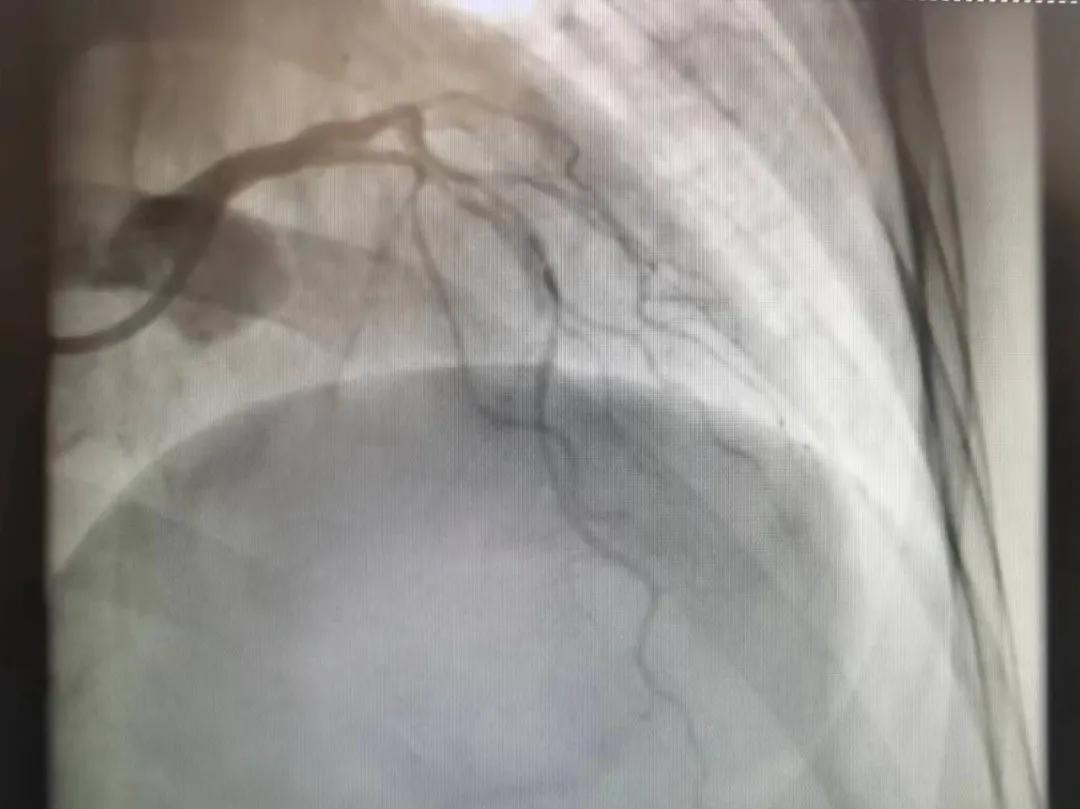

王瑾院長(zhǎng)和李慧新主任帶領(lǐng)介入團(tuán)隊(duì)充分評(píng)估,決定行前降支冠狀動(dòng)脈鈣化病變旋磨術(shù),術(shù)中應(yīng)用1.5mm旋磨頭,以15萬-17萬轉(zhuǎn)/分速度共對(duì)病變旋磨3次,累計(jì)旋磨時(shí)間60秒,后復(fù)查造影示鈣化明顯減輕,為后續(xù)操作創(chuàng)造了良好條件,隨后應(yīng)用預(yù)擴(kuò)張球囊、切割球囊再次處理病變,并順利植入支架1枚,復(fù)查造影顯示支架膨脹及貼壁良好,無夾層、血腫、慢血流等情況,手術(shù)順利完成?;颊咝g(shù)后無不適,胸悶、胸痛癥狀明顯緩解,順利出院。

術(shù)后